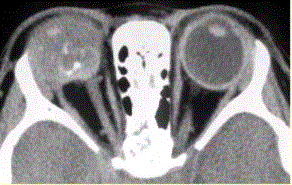

问题 患儿男,1岁,发现左眼白瞳2个月,头部CT显示如下图。 成视网膜细胞瘤的特征性CT表现是

选项 A.位于眼球内 B.伴视网膜剥离 C.增强明显 D.平扫高密度 E.软组织肿块内钙化

答案 E